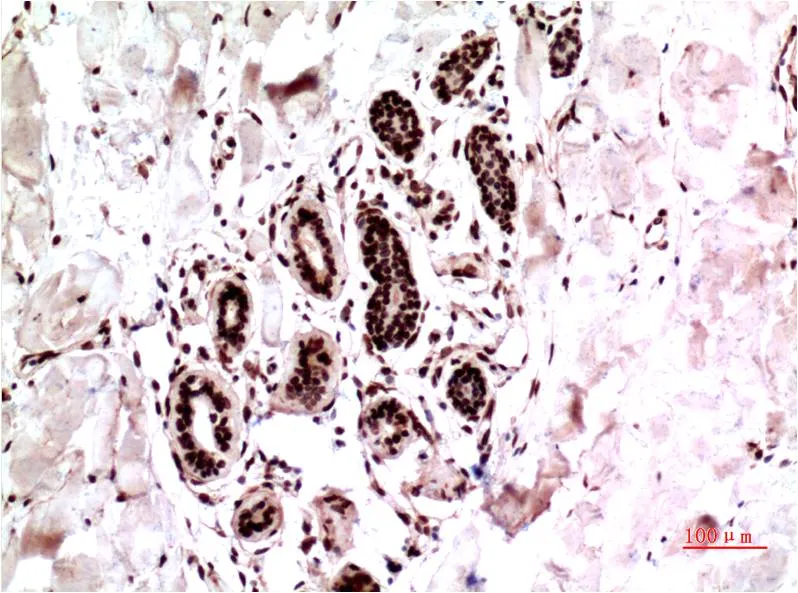

HDAC1 (3F5) Mouse Monoclonal Antibody

Cat: AMM03343

Size1:50μL Price1:$150

Size2:100μL Price1:$280

Size3:500μL Price1:$280

Application:IHC-P

Reactivity:Human,Rat,Mouse

Conjugate:Unconjugated

Gene Name:HDAC1